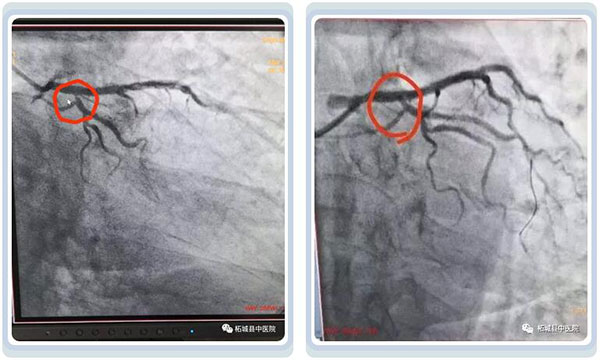

入院造影发现支架内再狭窄,原来植入的支架内又有高达99%的入口狭窄,北关院区心内科主任李建良、胸痛中心主任孙全立、主治医师张刘扛考虑其高龄已植入支架,不宜再植入支架也不适合冠脉搭桥,经讨论后,决定采用 先进的技术-药物球囊,对其再狭窄部位行药物球囊扩张,既达到“支架”扩张血管的目的,同时药物还能避免术后血管再狭窄,可谓一举两得,患者术后狭窄解除,胸痛症状消失,恢复良好。

▲术前术后对比,血管再通情况十分理想